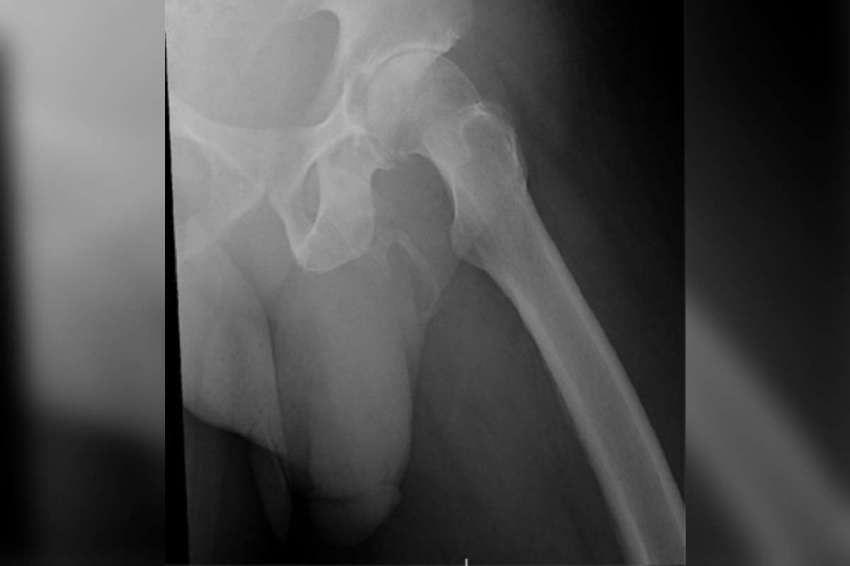

El paciente acudió al servicio de emergencias del Lincoln Medical and Mental Health Center del Bronx (Nueva York) porque se había caído cuando caminaba con su bastón por la calle. Una revisión pélvica descartó problemas en los huesos, pero encontró otro poco común: presentaba una "extensa calcificación (de los tejidos blandos) en forma de placa a lo largo del pene".

De acuerdo con el estudio publicado en la revista Urology Case Reports, el diagnóstico es claro: osificación de pene, una condición extremadamente extraña en seres humanos. Hay menos de 40 casos reportados en todo el mundo y vinculada tradicionalmente a la enfermedad de La Peyronie.